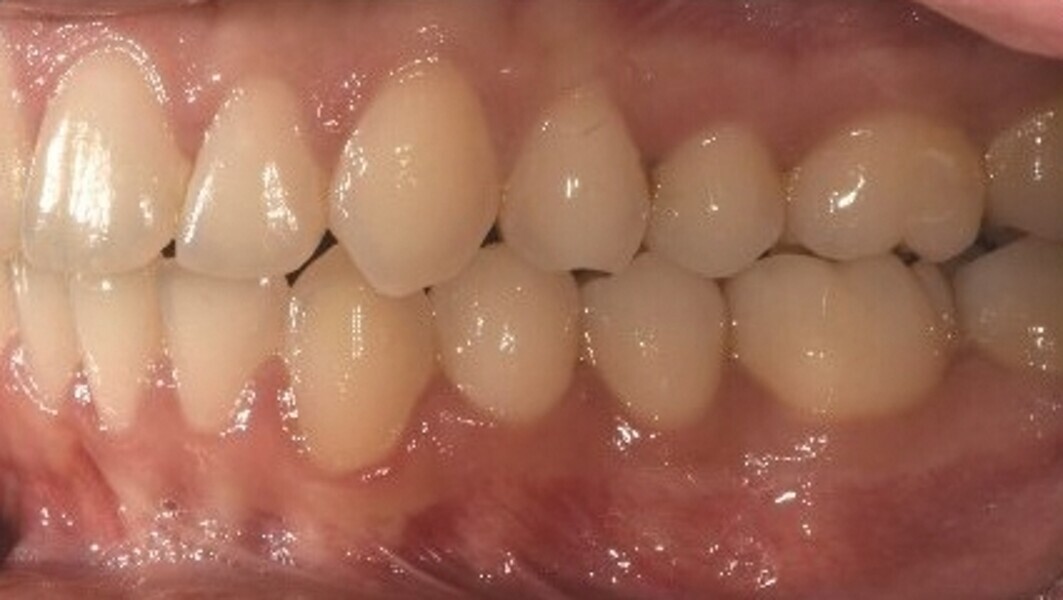

Le motif principal de consultation de la patiente, une jeune femme de 27 ans, est un encombrement dentaire accompagné d’une occlusion mal équilibrée. Danseuse de profession, elle se tracasse énormément au sujet de son apparence lors de ses apparitions publiques si elle entreprend un traitement. L’examen clinique révèle une relation d’Angle de classe I du côté droit et une relation molaire canine de classe II du côté gauche (Fig. 1).

De ce côté, les molaires, les prémolaires et la canine sont en occlusion croisée. L’examen ne montre aucun déplacement latéral fonctionnel de la mandibule. La ligne médiane maxillaire est en harmonie avec la symétrie faciale, mais la ligne médiane mandibulaire est déviée vers la gauche, en raison d’un décalage des dents de 4 mm. On observe un encombrement important des dents inférieures, évalué à 11 mm, et un encombrement modéré de 10 mm au niveau de l’arcade maxillaire. Les racines des dents 31, 33 et 43 semblent proches du rebord vestibulaire de l’os cortical, et les deux arcades présentent un rétrécissement dans la région des prémolaires et molaires.

Fig. 1c : Photographie intraorale initiale.